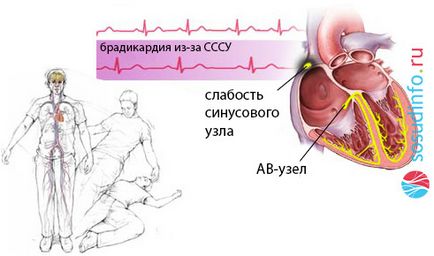

Példa MAC-szindróma miatt bradycardia

- Bradiaritmicheskaya formában - az impulzus csökken 30-20 percenként, és az ok általában a teljes a atrioventricularis block, sick sinus és teljesen leáll.

Amikor bradiaritmicheskoy formájában MSS kezelés magában foglalja az ideiglenes ingerlés és az atropin, a hiányában a hatást, amely látható aminofillin. Ha az eredmény negatív Ezeket a gyógyszereket a dopamin, epinefrin. Stabilizálódása után a beteg tekinthető állandó ingerlés.